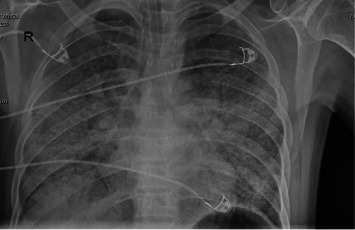

Introduction: People living with HIV (PLWH) are highly susceptible to respiratory infections, particularly pneumonia, which is often polymicrobial. A rapid decline in CD4 T lymphocytes, especially with concurrent influenza, increases the risk of Pneumocystis jirovecii pneumonia (PCP). Case Presentation: This report discusses a newly diagnosed Acquired Immunodeficiency Syndrome (AIDS) patient with influenza and PCP coinfection, highlighting diagnosis, follow-up, and prognosis. Conclusions: Community-acquired pneumonia is common in PLWH, especially among those not receiving antiretroviral therapies (ART). Co-infections with bacterial, viral, and fungal pathogens are common. Early identification of etiological agents and prompt treatment are crucial for improving patient outcomes.

Abstract Image